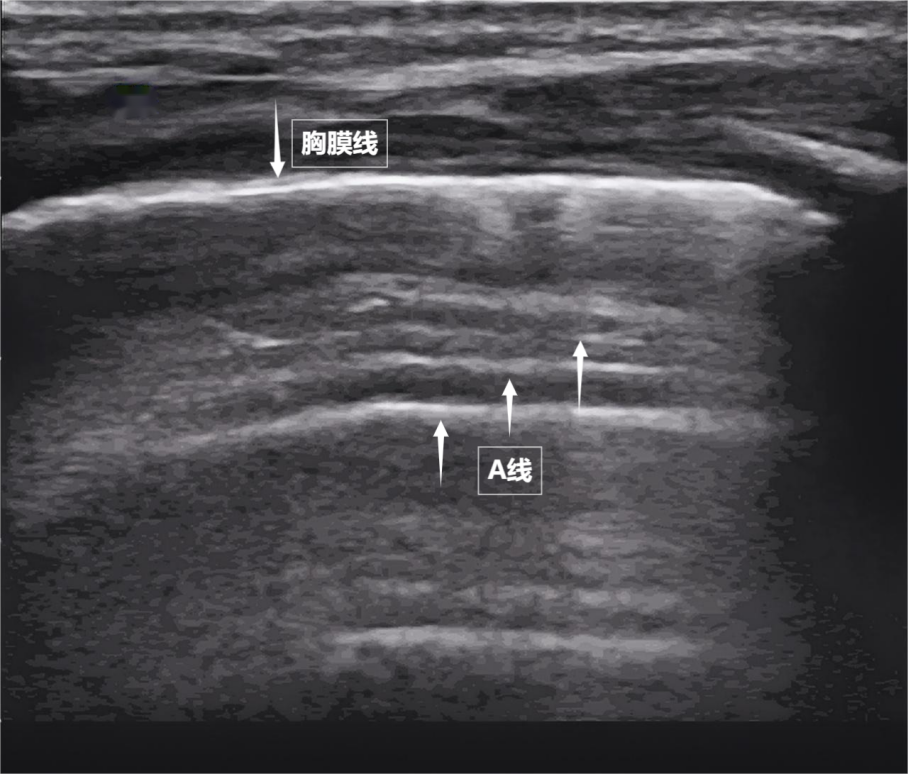

肺是我们体内的一对日夜工作的“风箱”。它们隐藏在胸腔深处,看不见,摸不着,但却与每一次呼吸的质量有关。医生如何“看肺部的状态?检查方法有很多种,但每种都有“缺点”:X光辐射、CT不宜移动、听诊器全靠医生经验……今天,我们就来介绍一种安全便捷的“透视眼”——肺部超声。这种“声探头”以无辐射、实时动态、床边检查等优势,成为观察肺功能的新窗口,不留痕迹却可挑要了解肺部超声波的细微变化,您必须首先了解一个基本原理:超声波通过“回声”产生图像。我们可以将超声波探头视为“声波扩音器”,它发出人耳听不到的高频波,这些声波穿过皮肤和肌肉。d当它们遇到体内的组织器官时,一部分会被吸收,一部分会返回。然后探头接收反弹的声波,计算机最终根据回声的强度、时间和方向在屏幕上构建动态黑白图像。然而,与肝脏和肾脏等实体器官不同,肺部充满了气体。空气是超声波的“天敌”——声波在肺部遇到空气时,大部分会被反射到气体后面,无法深入穿透。就像敲打充气的气球一样。你听到的是清脆的回声,但你在里面感觉不到它。因此,超声波一度被认为是“透过肺部看不见的”。但后来发现,当肺泡充满炎性液体(实变)、肺组织塌陷(肺不张)或胸膜腔内有液体积聚时,病变区域的气体被液体或聚集的组织取代,将原本被肺部气体阻挡的声波展翅起来,排斥病变部位,清晰地显示出病内病变的内部区域。病灶形成的“边界”构成了肺部超声诊断的基础。需要强调的是,肺部超声不能直接观察健康的充气肺组织。相反,它通过检查某些“伪影”(例如胸膜线和 A 线)来检查胸部肺壁交界处的动态变化。此外,它与常规乳房超声检查不同。胸部超声是一个更广泛的概念,涵盖所有胸腔内和胸周结构,如胸壁、肋骨、肺、胸膜和心脏。肺部超声重点检查肺部、胸膜和呼吸肌,是胸部超声的一个针对性很强的重要分支。谁需要肺部超声检查?虽然肺部超声检查很好,但并不是每个人都需要定期检查检查。它类似于“侦察”枪,在某些情况下很有用。以下人群特别适合进行肺部超声检查。急诊和危重症患者:对于突然出现呼吸困难、胸痛或外伤的患者,mabiDoctors可以通过肺部超声轻松判断他们是否患有气胸、胸腔积液或肺水肿。术后或长期卧床患者:有助于发现隐匿性肺炎、肺不张或血栓相关变化。心力衰竭或肾衰竭患者:监测肺水肿的存在和程度。儿童和孕妇:无需辐射,即可反复评估肺部状况。不明原因发热或感染率高者:帮助诊断肺炎、胸膜炎。考试前应该做哪些准备?考试前的准备工作非常简单。检查者需要穿着宽松的衣服,配合医生调整坐位或卧位,并平静地呼吸。无需禁食,无需注射kai物质成分,几乎没有禁忌症。超声波会使肺部疾病恶化吗?这是广大考生最关心的问题。答案很明确:肺部超声检查不会加重肺部疾病。它类似于“光侦察机”,利用声波传递信息,不留下任何“痕迹”。医学诊断超声波的能量很低,而且不含辐射——它不依赖于有害物质的“释放”,而是依靠人体组织能够探测到的声波的接收来创建图像,就像“用耳朵听回声”一样。目前尚无医学证据表明标准化肺部超声会对肺炎、气胸、肺水肿等肺部疾病产生不良影响,也不会损伤肺组织或引起炎症、呼吸功能弹。反之,可以安全、反复使用:是否需要动态监测的重症患者、对辐射敏感的儿童或孕妇,都可以放心接受超声检查。在肺部超声图像上可以看到什么?第一幕:《海岸线与海浪》——胸膜线和一条线。当声波穿过胸壁的肋骨间隙时,首先遇到靠近肺表面的光滑薄膜——壁层胸膜和脏层胸膜。两者紧密接触,中间没有多余的气体或液体。它们在屏幕上显示为明亮、平滑的水平线,共同形成胸膜线。这条线是肺部的“海岸”。在其下方,由于声波通过肺泡中大量气体的强烈反射,一系列均匀间隔、重复的平行于胸膜线的明亮平行线,像海浪一样向屏幕深处出现。这是 A 线(见下图)。 A字线是一个常见的标志正常通气的肺。它的存在直接表明肺表面含有足够的空气,胸膜腔内没有异常的液体或气体。该图像显示了正常新生儿肺部的超声表现。第二个场景:“波浪海滩”——滑动标志。如果我们以实时动态方式调整超声图像,将“图片”变成“电影”,就会出现更加神奇的场景。呼吸时,胸膜线会随着胸廓的运动而轻轻滑动。这就是“肺滑动征”。这意味着肺部与胸壁紧密相连,呼吸自由顺畅。如果肺壁和胸部之间存在气胸或胸腔积液,这种滑动就会消失。有时,胸膜线下方可能会出现一个小的亮白色闪烁点,称为“彗尾征”(见下图)。当它少量且孤立地发生时,通常是正常肺小叶间病变的反映。隔膜,无需担心。该图像显示了正常新生儿肺部的超声表现。第三幕:“呼吸动力泵”——呼吸肌肉的协调运转。呼吸看似简单,但实际上是多组肌肉共同协作的“集体运动”。肺部超声不仅可以观察肺部的形态,还可以通过实时动态图像“捕捉”肺部呼吸肌的活动状态,为呼吸功能的评估提供了独特的视角。膈肌是呼吸肌的“总指挥”,位于胸腔和腹腔之间。平静呼吸时,膈肌收缩下沉,胸腔容积扩大,空气自然吸入;放松时,横膈膜上升,肺部弹性收缩以完成呼吸。在超声波下,可以看到隔膜光滑且呈拱形,向上移动随着呼吸节奏下降(见下图)。肋间外肌是“肋间肌”的“提升间隙”,收缩时将肋骨抬高,扩大胸部前后径,有助于吸气。这个“黄金搭档”承担着日常呼吸70%以上的工作量,是维持呼吸的“首要力量”。图为当身体需要更多氧气(如上楼梯)时横膈膜的正常超声表现,斜角肌和胸锁乳突肌得到“强化”。在严重的情况下(例如哮喘发作),腹壁肌肉和肋间内肌会被调动。肺部超声这个“侦察兵”,可以通过观察肌肉激活的顺序、测量膈肌的厚度和活动度,获取肌肉的矛盾运动来评估呼吸肌的变化,从而发现呼吸系统“过度运转”的早期迹象,为医生调整治疗方案提供准确依据。来源:健康中国。